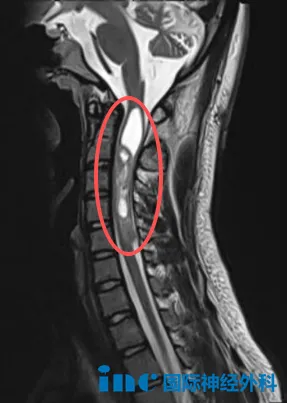

18岁的帆帆,自2009年起便走上了一条充满挑战的求医之路。4岁那年,他接受了第一次手术,切除了头顶的神经鞘瘤。14岁时,确诊神经纤维瘤病2型,进行了右侧小脑病损切除术。2022年10月以来,帆帆反复出现右下肢剧痛,严重时疼痛可持续约6小时,难以入睡;还伴有进行性听力下降的困扰。今年7月的复查显示,其后颅窝、颈椎椎管及胸壁多处病灶仍有进展,右颈部病变大小约7.0cmx5.2cm。面对疾病的反复考验,这个少年有着超乎年龄的坚韧,而他的家人始终是他最坚强的后盾,用不离不弃的陪伴给予他前行的力量。

在咨询巴教授后,他们了解到需要分次手术应对多处病灶。由于颈髓病灶持续进展可能面临瘫痪风险,首次手术将优先处理该部位。面对面交流,教授的回复给予了他们极大的信心,更赋予了他们决策的勇气。